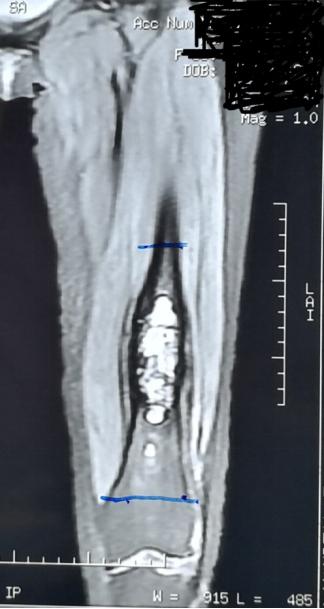

胡勇教授指出,对于股骨远端肿瘤切除后的重建问题,目前通常采用金属假体置换来解决,但其术后功能无法媲美原有关节,关节寿命有限,可能面临多次手术翻修等问题。本例手术方案我们保留了患者原有膝关节,采用自体带血管腓骨复合大段异体骨移植重建,达到了生物学重建的标准。

大段异体骨复合带血管腓骨用于四肢长骨骨缺损重建的力学和生物学优势,在力学方面,早起大段异体骨的载荷与中晚期带血管腓骨愈合后的载荷互补,为重建后功能康复过程中的不同阶段的力学支撑提供保证。在生物学方面,大段异体骨提供了骨量和生物学支撑体;血管化腓骨作为活骨其愈合过程无须爬行替代;血管化腓骨为大段异体骨提供了内活化表面, 并可促进异体骨和宿主骨断端愈合。